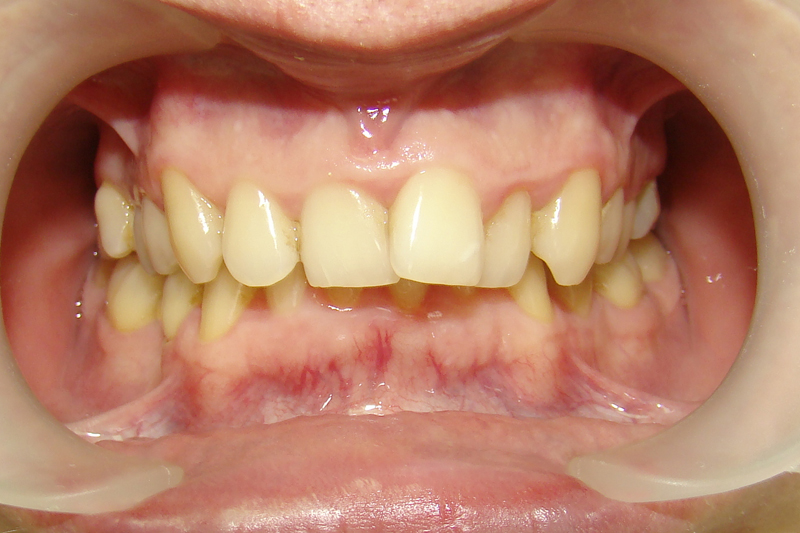

Покажу клинические случаи, чтобы было проще представить возможности ортодонтического лечения.

А это уже молодой человек 10 лет. Тоже получилось справиться без удаления. Хоть оно и было показано. Но мальчик очень упорно носил специальные аппаратики и резиночки. Покажу со всех сторон. Этот случай победил в конкурсе на конференции

Молодая девушка и очень мне нравится результат!